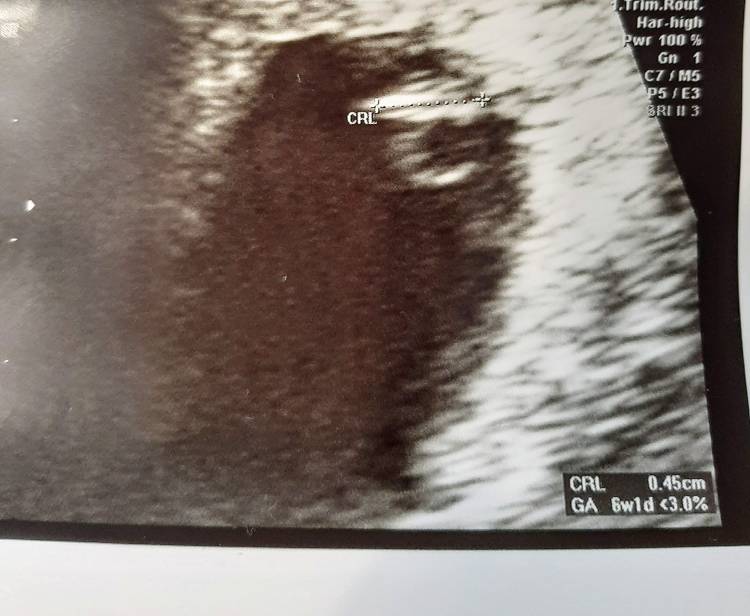

Cały dzień w pracy, odbiór dzieci a potem wizyta i było serduszko! ❤️ Troszkę zmodyfikowaliśmy wiek ciąży i umawiamy się ze to jednak 6 tygodni skończonych. Jest karta ciąży i szereg badań do zrobienia w ciągu najbliższych tygodni. No i tez pappa ze względu na wiek :) cieszę się bardzo i planuje jutro przyjaciółkom powiedzieć :))) dziś byłam u mamy ale jakos mnie nie natchnęło na podzielenie się i waham się czy mówić czy nie.